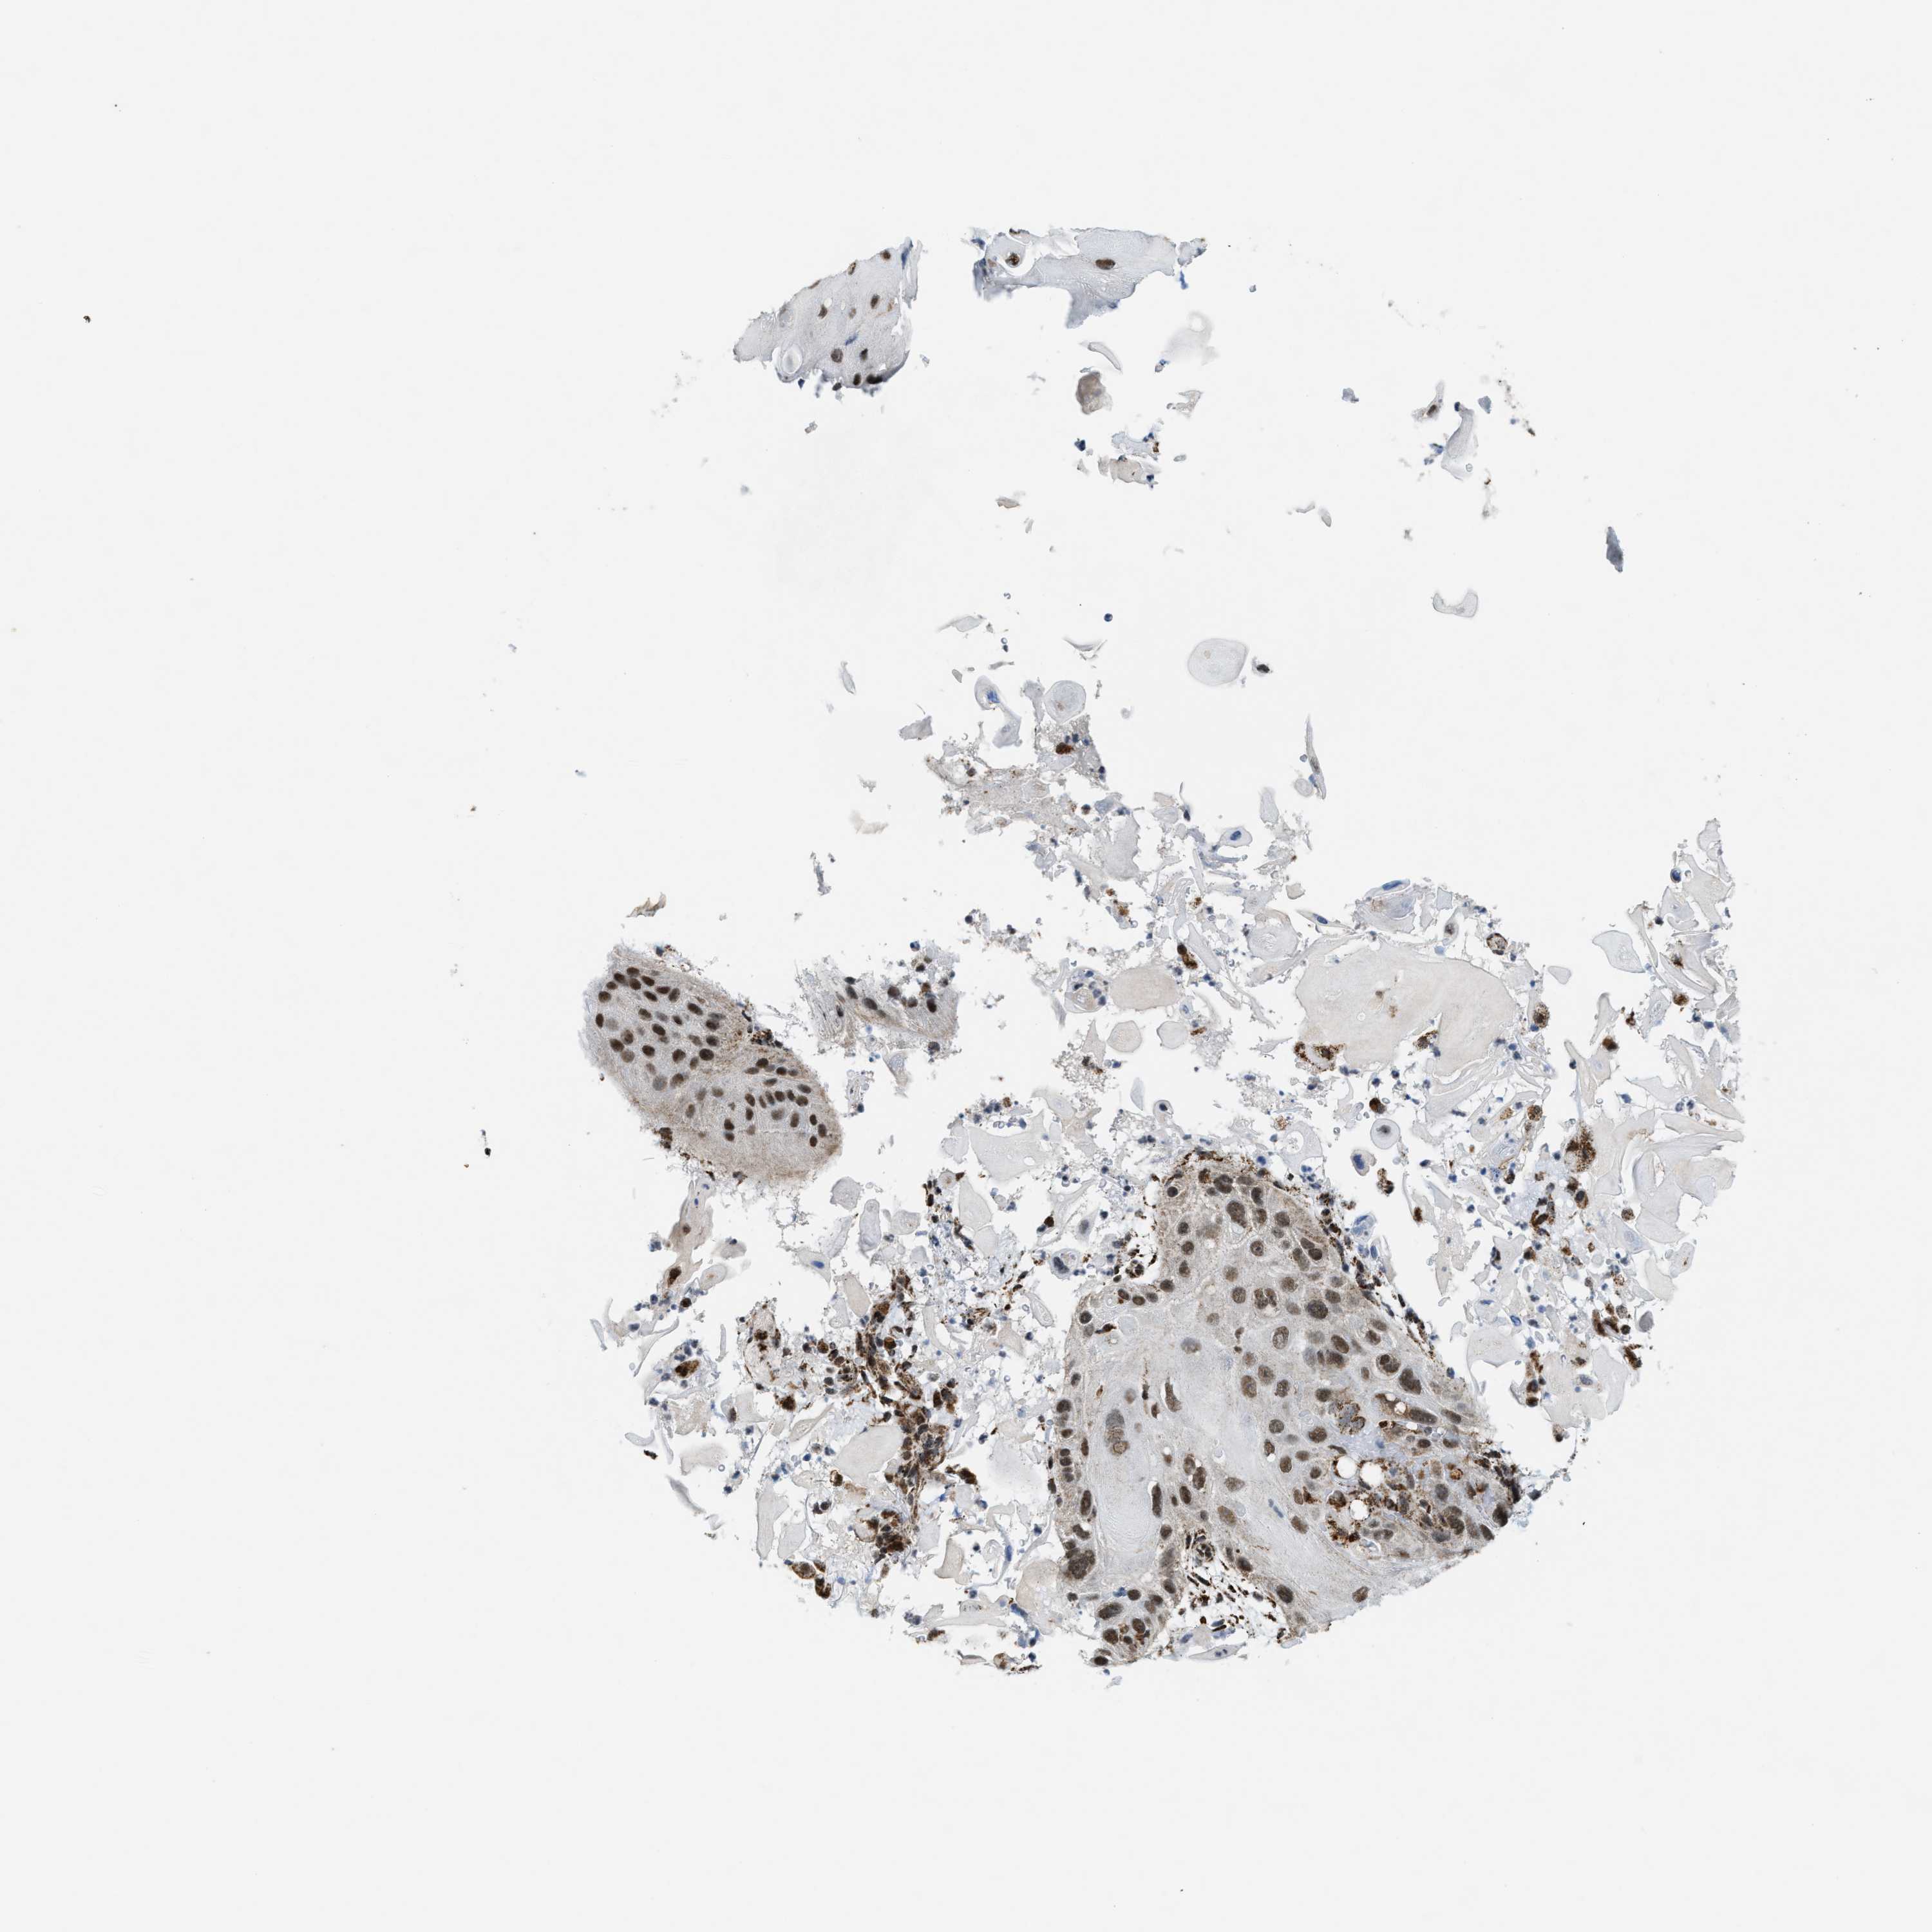

SKIN CANCER - Protein expressioni

A mouse-over function shows sample information and annotation data. Click on an image to view it in a full screen mode. Samples can be filtered based on level of antibody staining by selecting one or several of the following categories: high, medium, low and not detected. The assay and annotation is described here.

Antibody stainingi

Antibody staining in the annotated cell types in the current human tissue is reported as not detected, low, medium, or high, based on conventional immunohistochemistry profiling in selected tissues. This score is based on the combination of the staining intensity and fraction of stained cells.

Each image is clickable and will lead to virtual microscopy that enables deeper exploration of all samples and also displays staining intensity scores, fraction scores and subcellular localization as well as patient and tissue information for each sample.

Antibody HPA019522

Antibody HPA021002

Staining

High

Intensity

Strong

Moderate

Weak

Quantity

>75%

75%-25%

<25%

Location

Nuclear

Cytoplasmic/membranous

Cytoplasmic/membranous,nuclear

Squamous cell carcinoma in situ, NOS

Squamous cell carcinoma, NOS

Squamous cell carcinoma, metastatic, NOS

Basal cell carcinoma